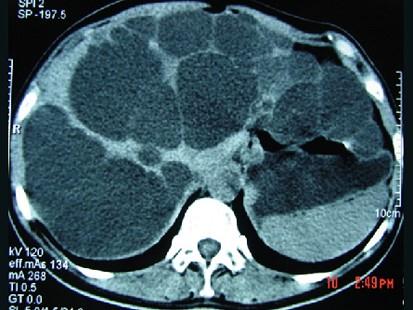

问题 女,20岁,右上腹胀,影像表现如图,最可能的诊断是 ( )

选项 A、肝脓肿并肾囊肿 B、多发性肝囊肿并多发性肾囊肿 C、多囊肝并肾多发囊肿 D、肝淋巴管瘤并多发性肾囊肿 E、先天性肝内胆管扩张并多囊肾

答案 C